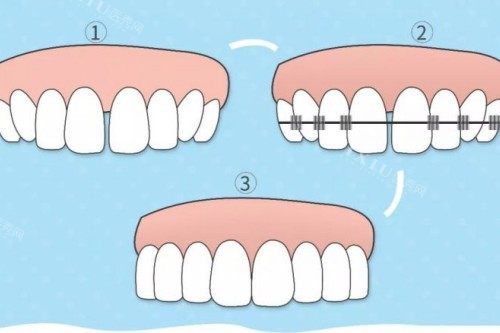

MBT 托槽,全称为 “美容正畸托槽”,是由正畸领域的三位骨干医生共同研发的成果。它的设计独具匠心,着重于减小摩擦力,以此提升牙齿移动的效率。其特殊的槽沟设计,就像是为牙齿量身定制的轨道,能帮助牙医更轻松地进行个性化矫治。无论是简单的牙齿不齐,还是复杂的矫正病例,MBT 托槽都能展现出出色的表现。

Roth 托槽采用了深槽设计,如同坚固的堡垒,强调对牙齿的稳定性与控制力。在转矩和轴倾方面,Roth 托槽的调整精度较高,这使得它在拔牙矫正的病例中表现不错。不过,这种托槽相对来说更考验医生的技术,因为其操作复杂性较高,需要医生具备优质的技艺和丰富的经验。

MBT 托槽以 “小摩擦” 为核心设计理念,就像给牙齿安装了一个顺滑的跑道,减小托槽与钢丝之间的摩擦力,促使牙齿能够快速矫正。而且,它的隐形设计,就像给牙齿穿上了一件隐形衣,受到许多追求美观的求美者的青睐。

Roth 托槽则重视托槽与钢丝间的紧密结合,通过强固的槽沟,如同给牙齿加上了精密的导航系统,使牙齿在矫正过程中实现严谨的转动与倾斜矫正。

MBT 托槽适用于多种牙齿畸形,尤其是那些需要复杂矫正的患者。它的粘接技术简单,就像搭积木一样轻松,且舒适度高,患者在佩戴的时候更容易适应,仿佛牙齿在不知不觉中就变整齐了。

Roth 托槽更适用于需要拔牙矫正的病例,因为其转矩成效更佳,能够精密地控制牙齿的移动。然而,由于设计复杂,其适用人群相对更小。